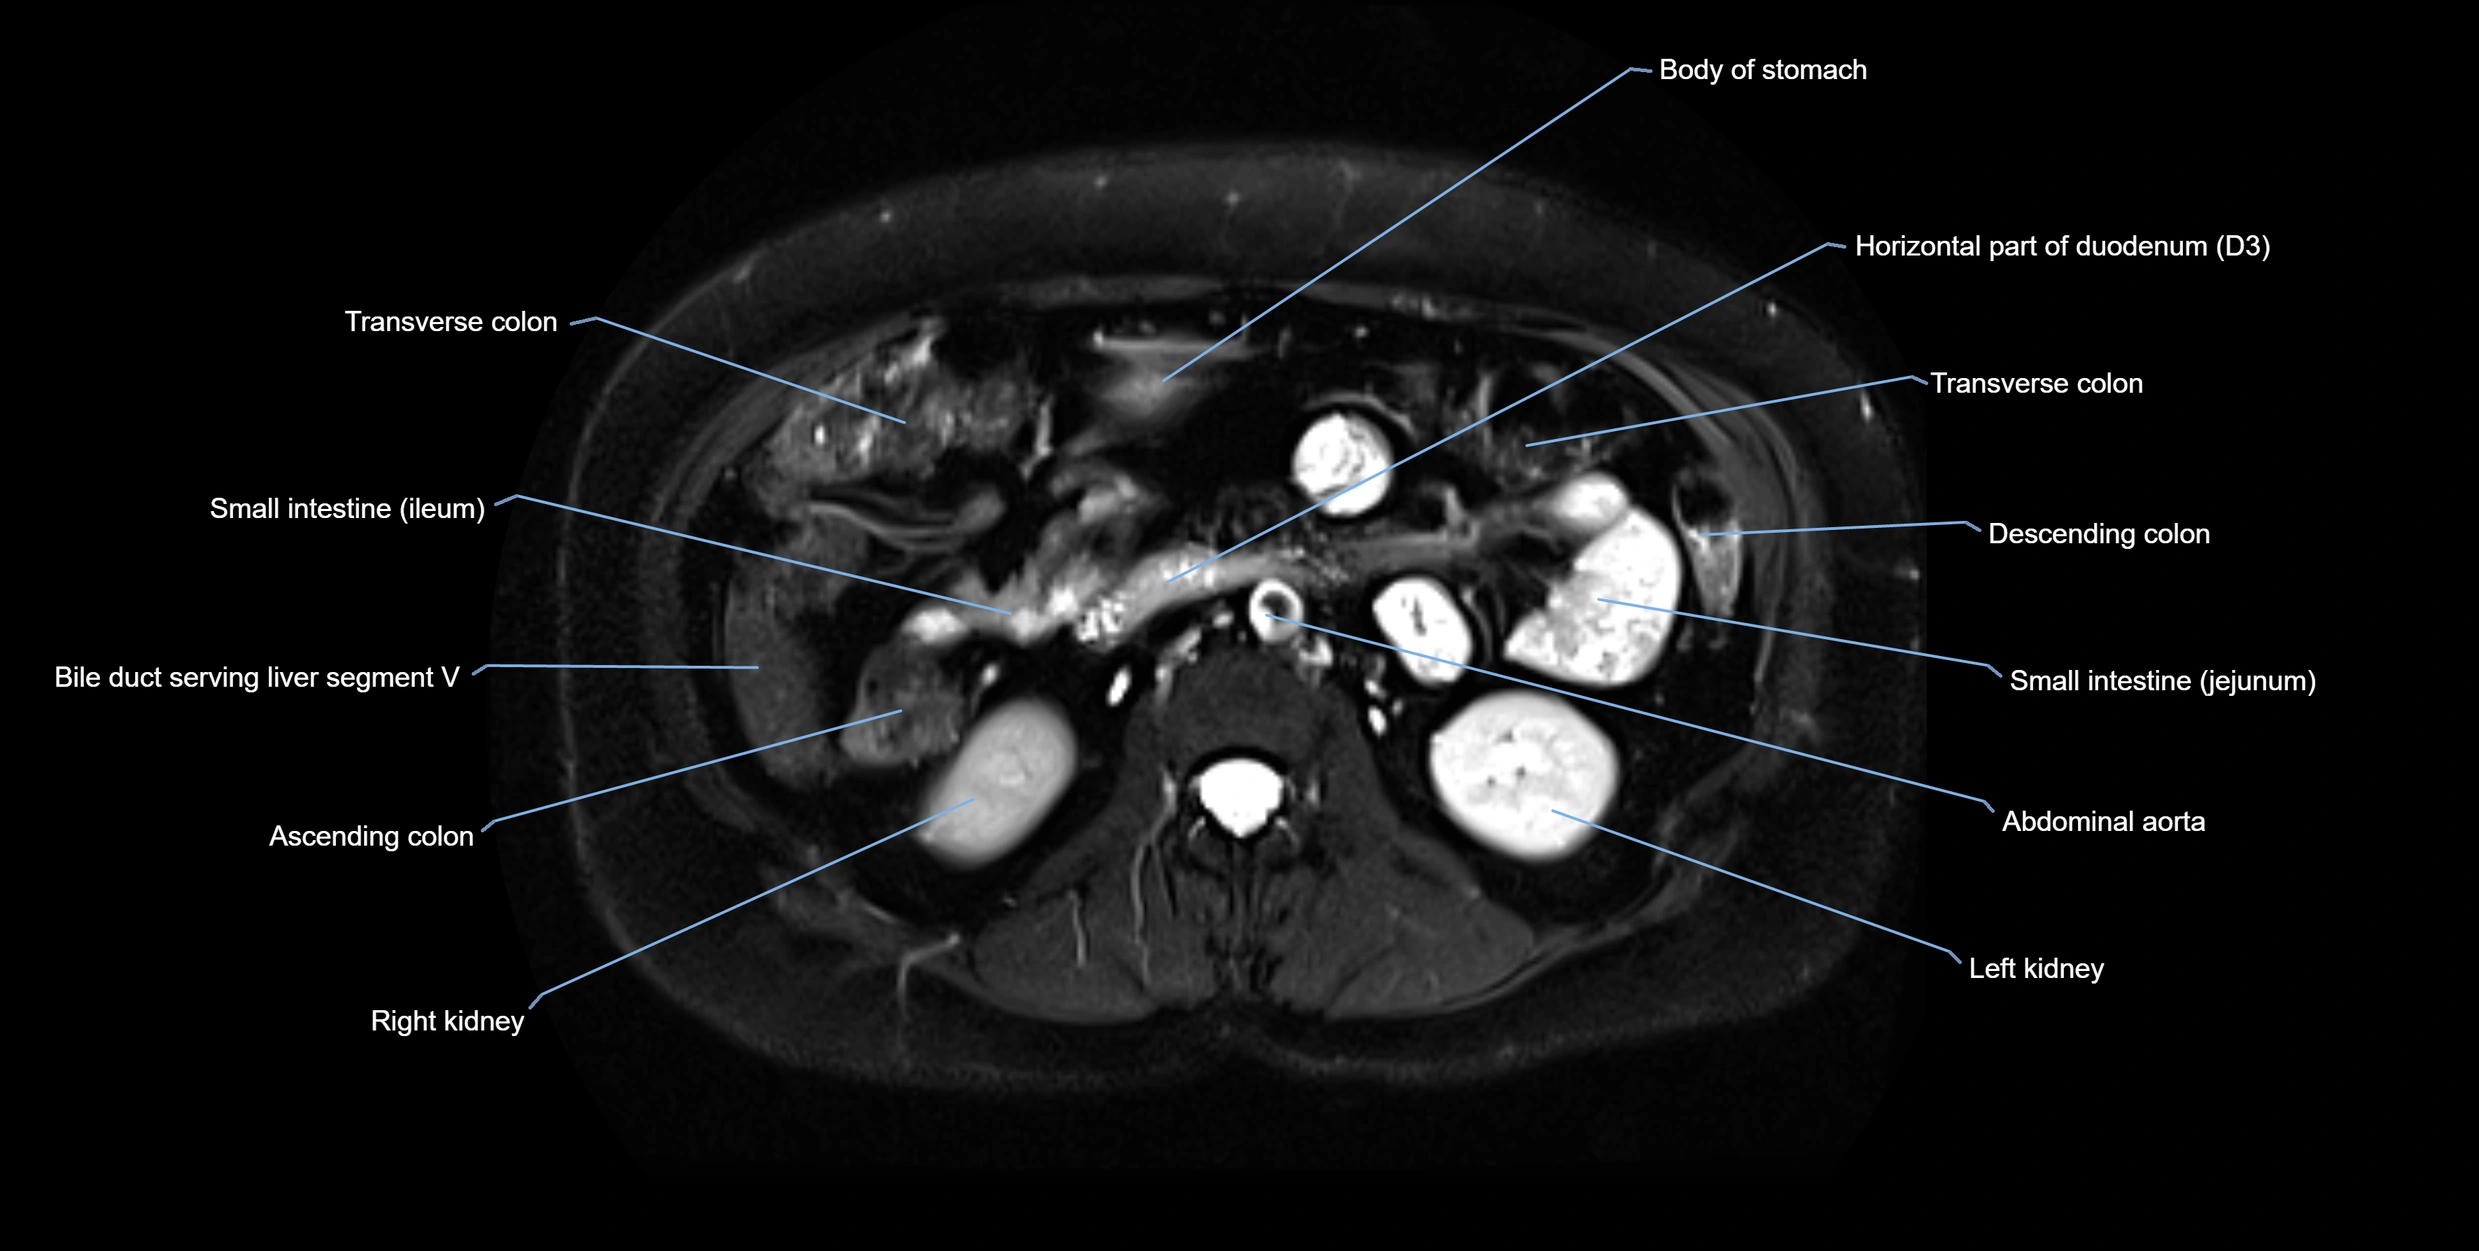

MRI image

image